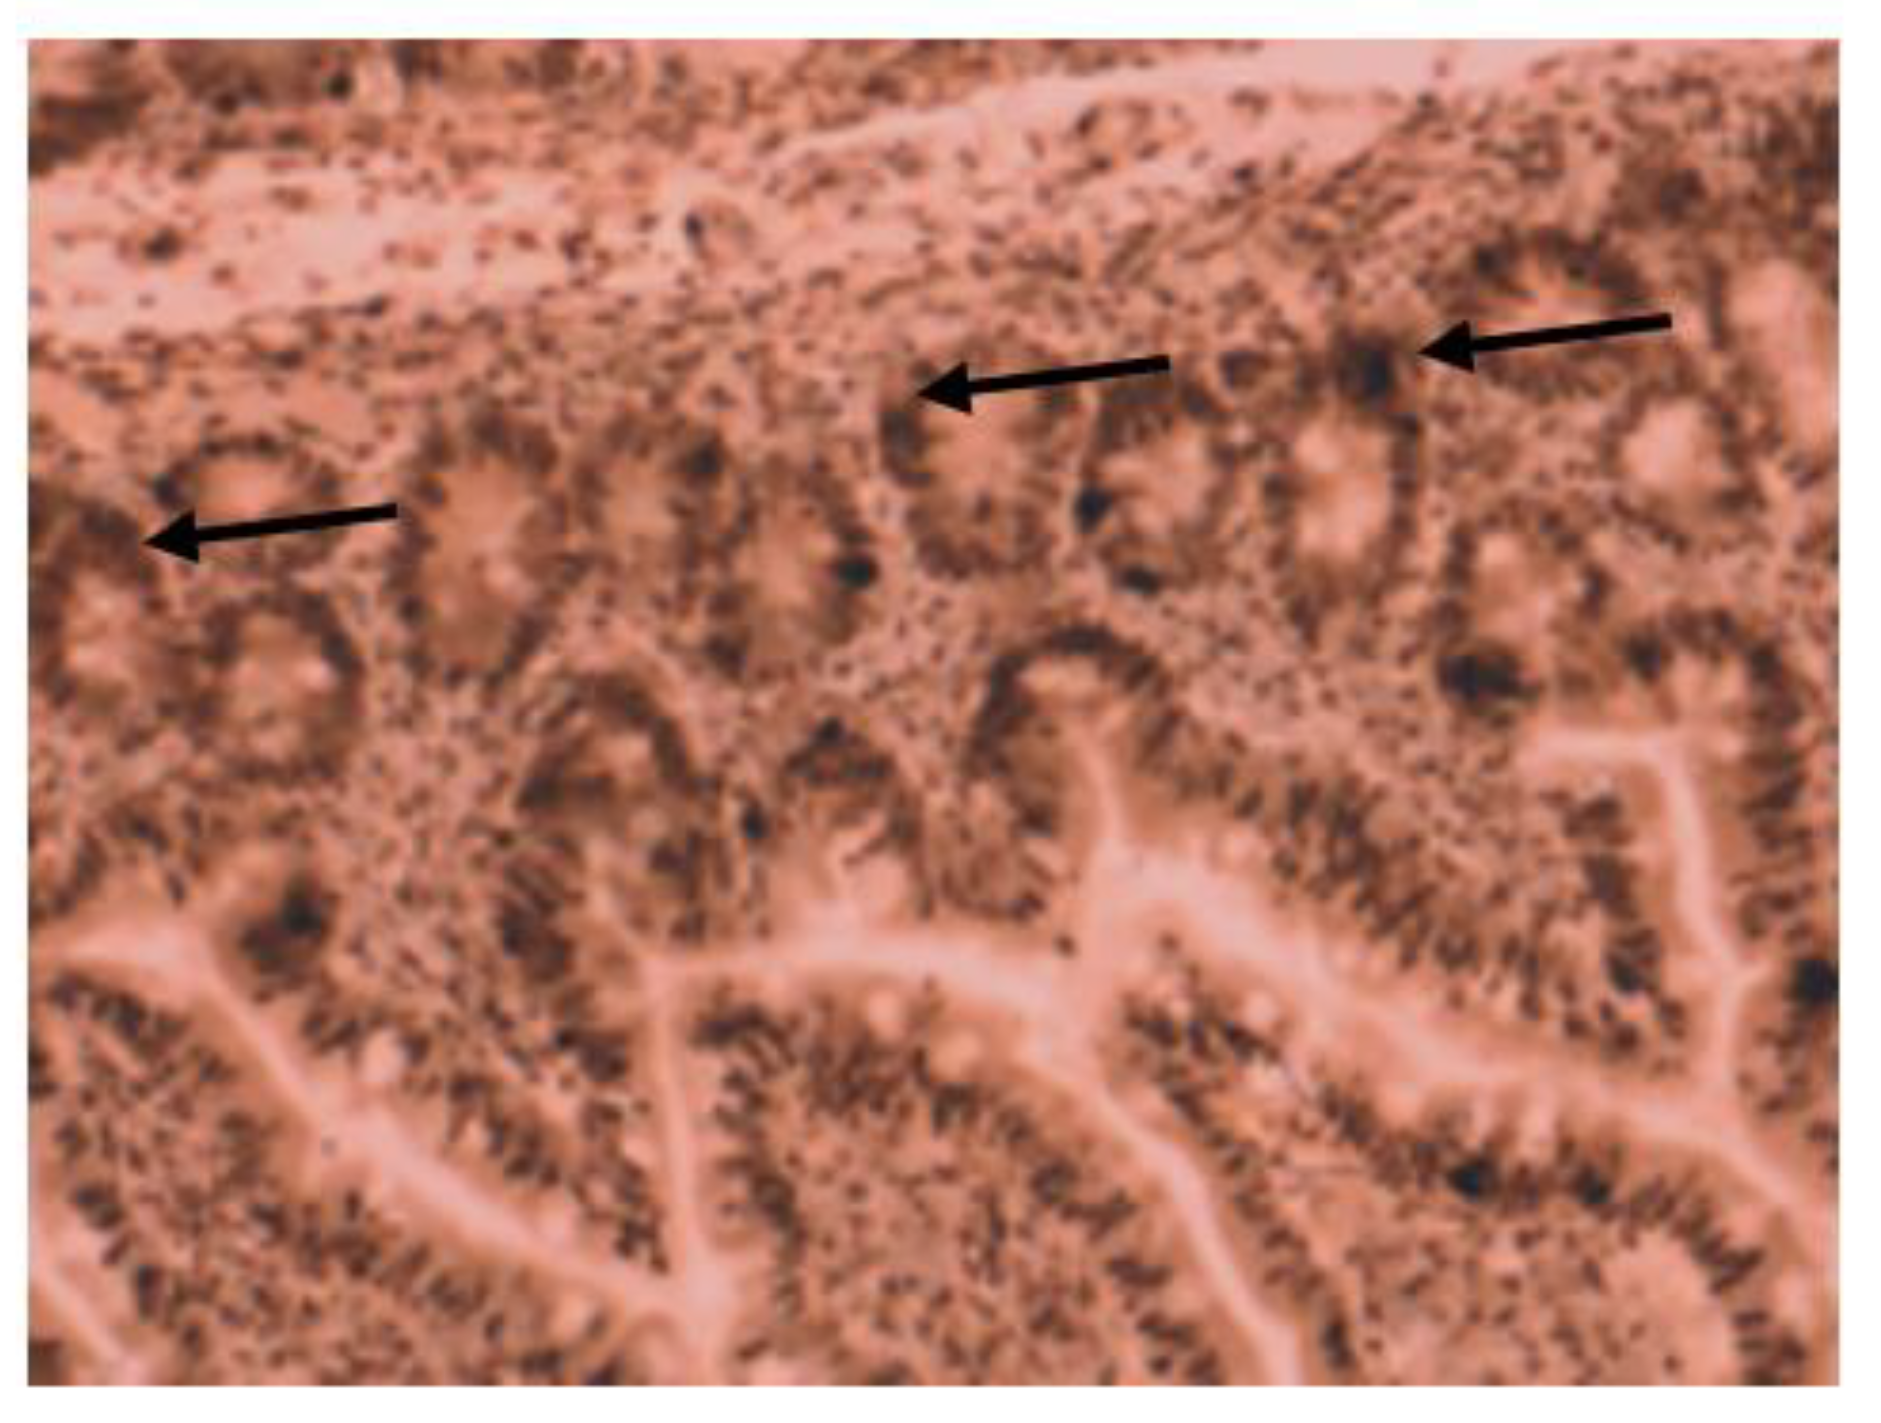

Medium VDR nuclear expression was high in normal colon (45%), while it was low in colorectal tissues of patients with IBD (33.7%). In colon tissue of patients with Crohn’s disease (Figure 3), medium VDR nuclear expression was 35.5%, and in colon cells of patients with ulcerative colitis (Figure 4), it was 32.65%.

Figure 3.

Immunohistochemical image of VDR expression in colon tissue of a patient with Crohn’s disease.